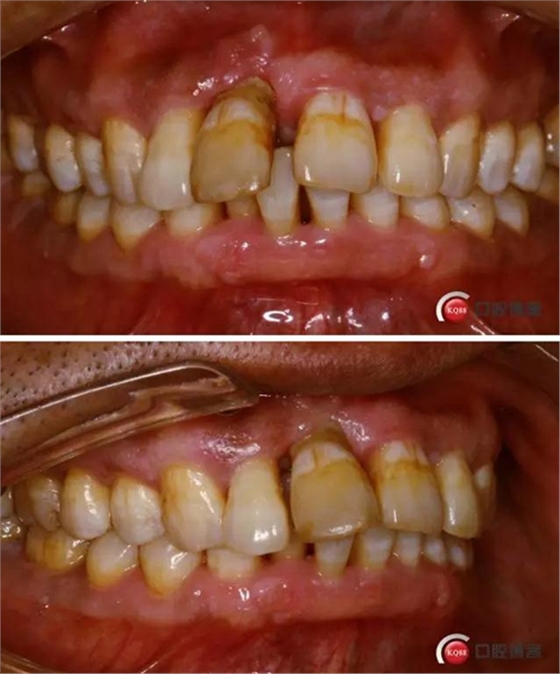

患者:王XX 年齡:42 上前牙松動數(shù)年,從未做過任何處理,今來院就診;檢查:CBCT示上前牙區(qū)顎側(cè)一大小約7x7mm囊腫;治療計劃:即刻種植同期摘除囊腫

術前口內(nèi)照